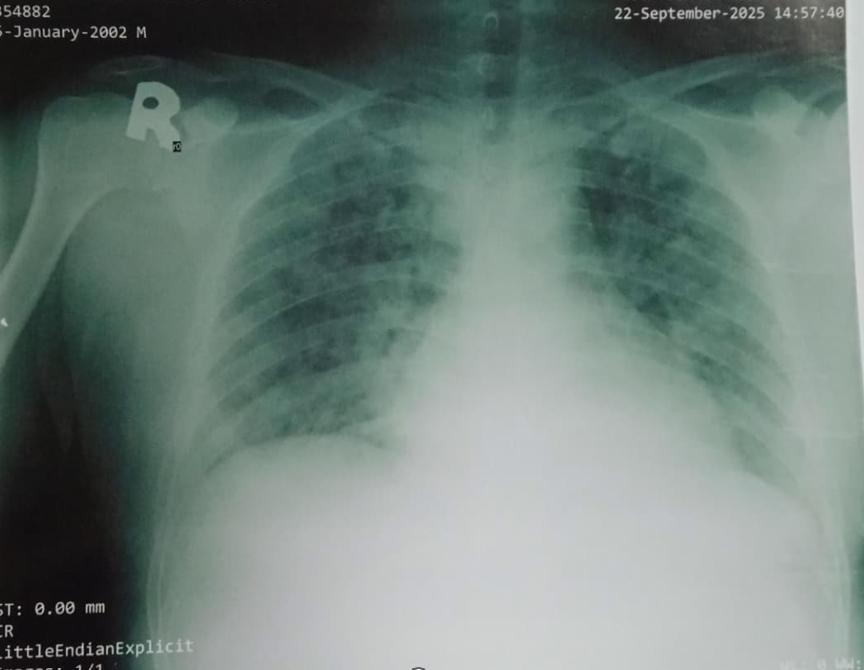

Relevant Test Results Prior to Catheterization

STEMI was initially unrecognized, and no ECG was performed for over 24 hours. As symptoms worsened, ECG showed anterior STEMI and Troponin I was elevated. Echo revealed LVEF 45% with akinetic mid–apical LV segments. Due to respiratory distress, myocarditis or contusion was suspected. Cardiac CT confirmed total LAD occlusion. The patient received Fondaparinux, aspirin 300 mg, and clopidogrel 300 mg before PPCI.